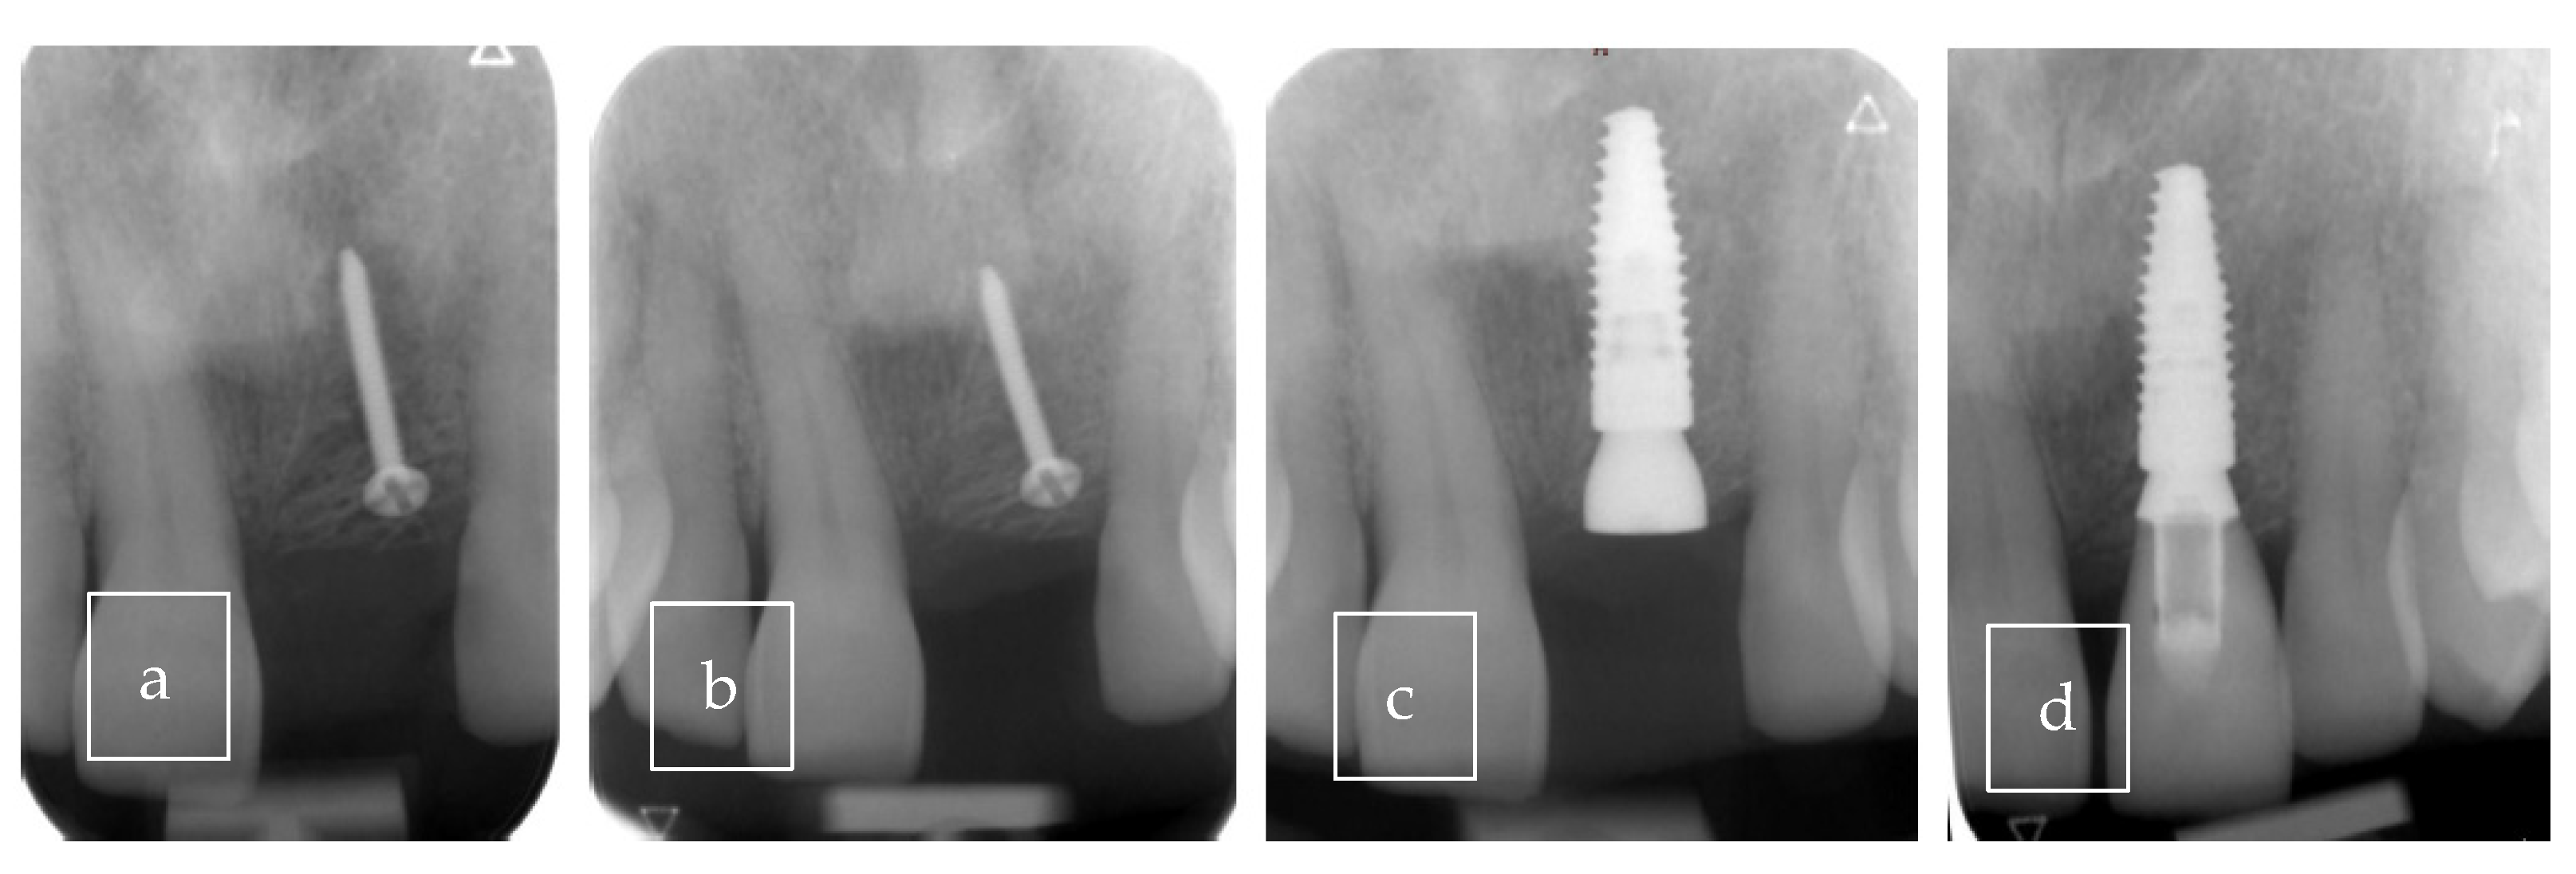

| Our case | Case report | 1 | M | 63 | Asymptomatic | Right palate | Surgical excision | 9 × 8 × 12.5 mm | Radiolucent |